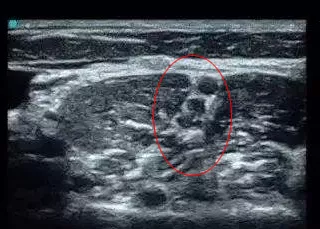

简单来说,就是在B超的引导下,以药物麻醉臂丛神经,在患者没有痛觉的状态下,再实施手法松解。整个过程只需5分钟,且效果立竿见影。

在B超的引导下,对林阿姨的臂丛神经实施麻醉